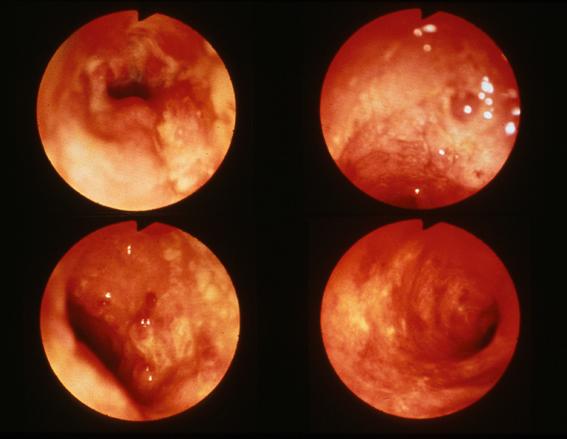

A case of left side ulcerative colitis

Tokyo Pref., Cooperative study between National Cancer Center and Kyushu Cancer Center

Inflammatory or ulcerative disease / lesions/Ulcerative colitis

Large intestine(Colon)/More than one of the above

Endoscopy